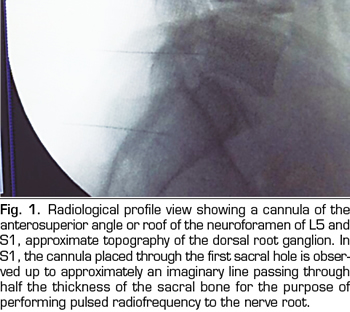

The procedure was performed in the surgical room in ventral decubitus position. A peripheral venous catheter and standard monitoring were placed. The C-shaped arch was used for the location of the DRGs through the anteroposterior, oblique and profile approaches (Figures 1 and 2). A Cosman G4 radiofrequency generator was used. Radiofrequency cannulae number 22 or 20, 10 or 15 cm length respectively, were used, based on the patient’s size, with 1 cm of active tip. The radiofrequency cannula was placed on the anterior-superior side or roof of the selected neuroforamens (Figure 1). In the case of S1, the cannula was placed in the first sacral foramen and the radiofrequency of the nerve root was performed, instead of approaching the dorsal root ganglion through the sacrum, because this is considered excessively invasive. The needle was deepened to an imaginary line located in the middle of the thickness of the sacrum (Figure 2).